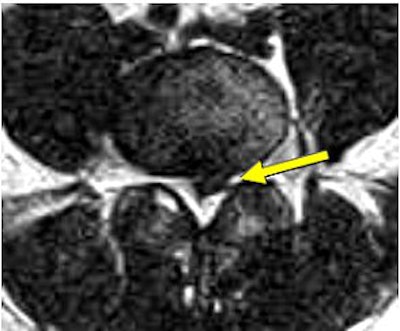

![]() |

| Above, preaxial loaded. Below, axial-loaded image. Central subligamentous disk herniation and discogenic disease at L5-S1 impressing the thecal sac only after axial loading is applied. L4-L5 bulging, discogenic disease, and a central subligamentous disk herniation impressing on the thecal sac. Bulging and discogenic disease at all other levels. |